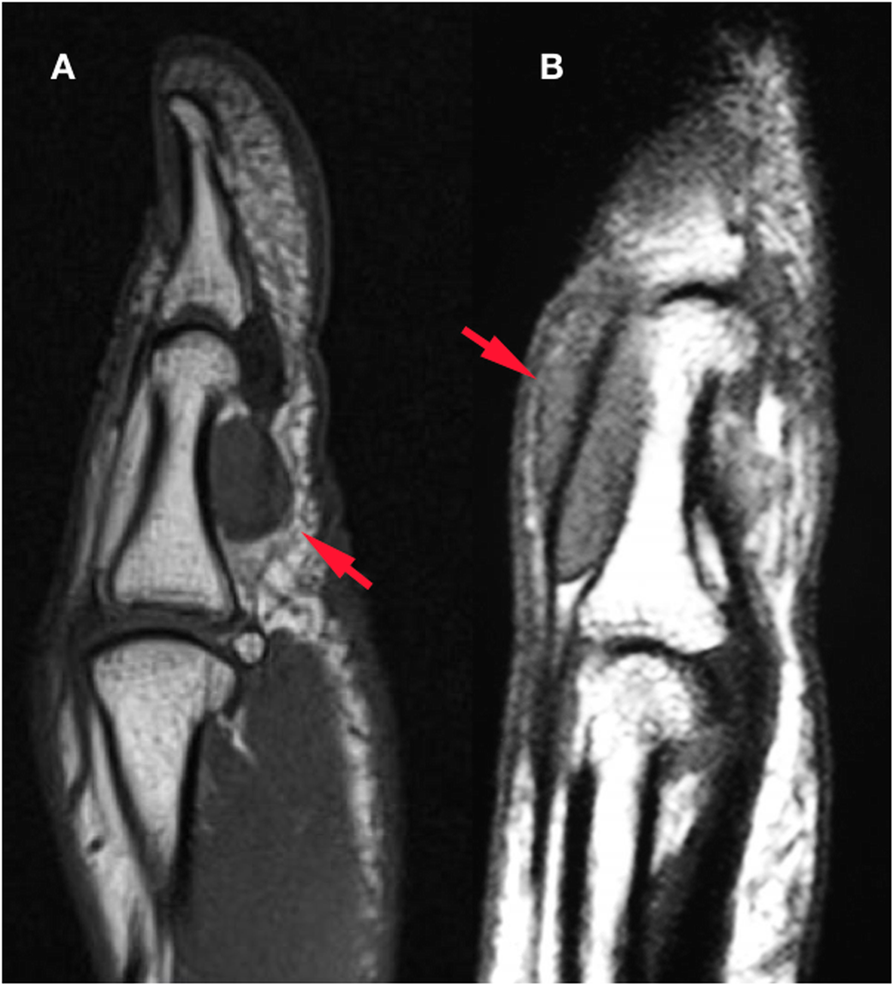

t(1;2)-Positive Localized Tenosynovial Giant Cell Tumor With Bone Invasion | In Vivo